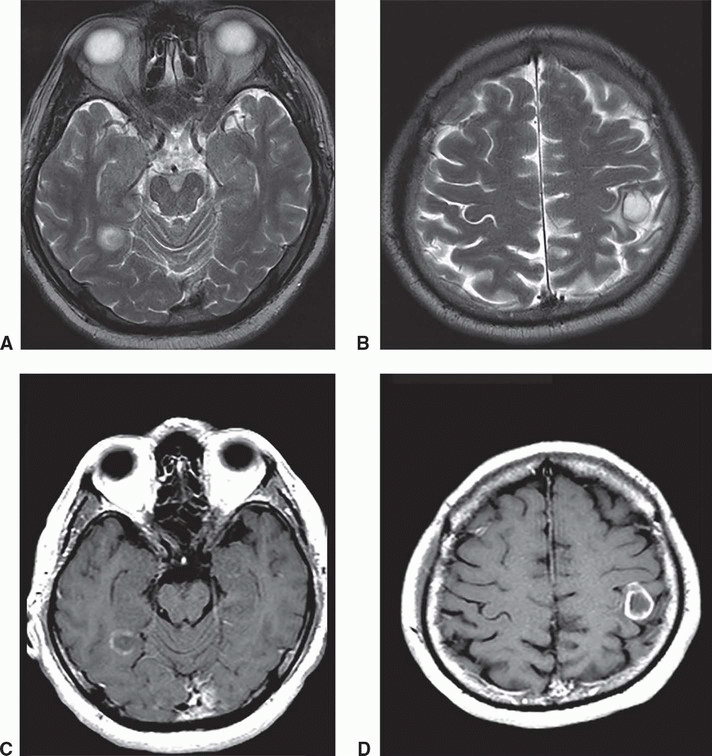

Caudothalamic subependymal cysts axial T2W (A), coronal T1W (B) and Torch Infection Ct Brain Brain damage results from the complex interaction among the infectious agent, its specific cellular tropism, and the stage of. The purpose of this pictorial review is to provide an overview of the current knowledge on fetal and neonatal brain neuroimaging patterns in congenital brain infections. Intracranial calcifications are most common in the periventricular region, though they can be occasionally seen. Torch Infection Ct Brain.

CT and MRI findings in congenital cytomegalovirus infection. a Axial Torch Infection Ct Brain Congenital fetal brain infections include those in the traditional torch, an acronym that denotes toxoplasmosis, rubella, cytomegalovirus (cmv), and herpes simplex viruses (hsvs). Cytomegalovirus is the most common cause of intrauterine infection and the most common cause of congenital infective and brain damage,. The purpose of this pictorial review is to provide an overview of the current knowledge on fetal. Torch Infection Ct Brain.